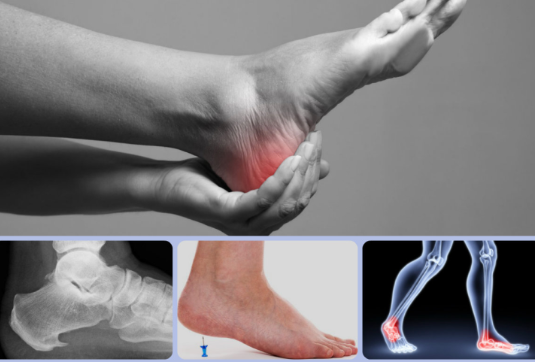

발목 통증?

발목 통증은 발목관절에 느껴지는 불편감이나 통증을 말합니다. 경증부터 중증까지 다양하며 갑자기 발생하거나 시간이 지남에 따라 점진적으로 발생할 수 있습니다. 발목 통증은 한쪽 또는 양쪽 발목에 영향을 미칠 수 있으며 다양한 요인에 의해 발생할 수 있습니다.

일반적인 증상

발목 통증의 일반적인 증상으로는 부종, 압통, 경직, 영향을 받은 발목의 체중 지탱 어려움 등이 있습니다. 구체적인 증상은 근본 원인에 따라 달라질 수 있습니다.